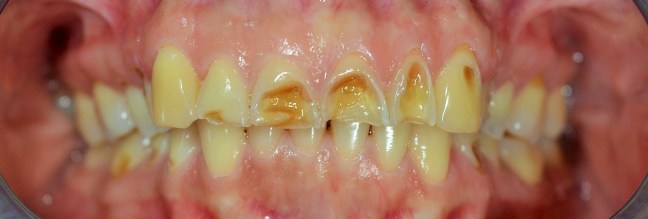

Kozmetikai kezelés: régi tömött, szuvasodott frontfogak szanálása, koronával történő leplezése, megsüllyedt harapás korrekciója.

A választott korona típusa: E-max préskerámia (fémmentes) és cirkon szóló koronák kombinációja.

A választott fogszín A1 .

A protetikai munka elkészülésének ideje: 5 munkanap.